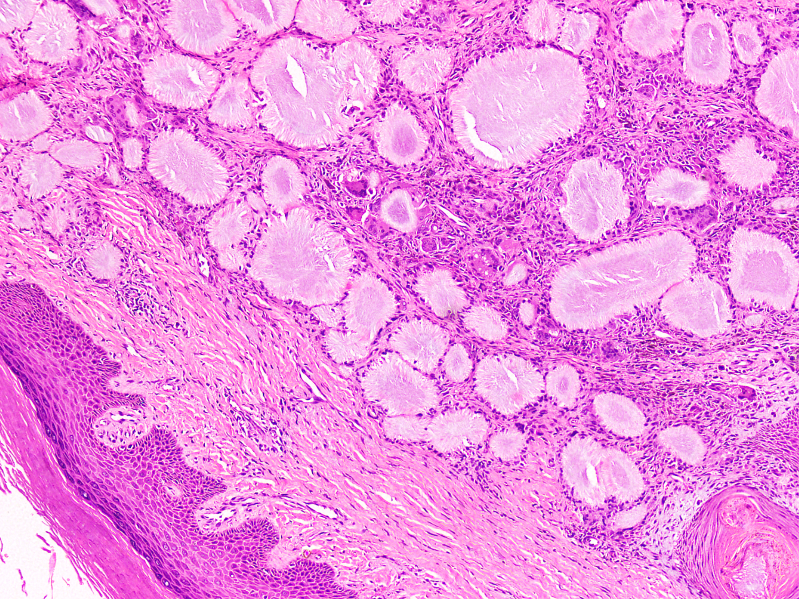

Microscopic (histologic) description

- Gout tophus:

- Nodular aggregates / granuloma-like appearance consisting of acellular, amorphous, pale eosinophilic material surrounded by palisading arrangement of histiocytes and multinucleated giant cells (Dermatol Online J 2015;21:13030)

- Feathery appearance in some deposits due to empty needle shaped spaces (Skeletal Radiol 2020;49:1325)

- Presence of monosodium urate crystals (MSU) is diagnostic

- Needle-like crystals that measure 5 - 25 micrometers in length

- Brightly anisotropic under polarized light

- Negative birefringence when examined with an interference plate in the light path (Otol Neurotol 2009;30:127)

- Crystals appear yellowish when aligned parallel to the plate axis

- Bluish appearance when alignment is across the direction of polarization

Microscopic (histologic) images